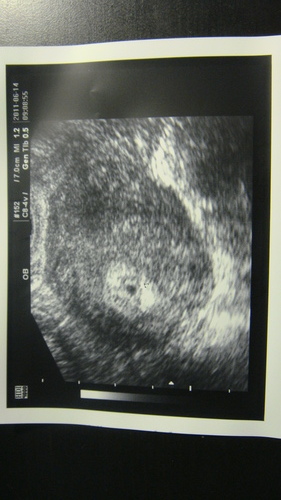

6/21回診照超音波 整個禮拜都在擔心受怕~好怕上次看到的小黑點會不見

沒想到一個禮拜不見~已經長大不少~胚囊有1.41CM囉!

醫生用大小推估約5~6W大 大概五月底受孕(跟我的基礎體溫是一致滴)

約了7/5(兩週後)回診聽心跳~比中醫預估的7/10還早哩~~

5W3D 小不點長成變形蟲